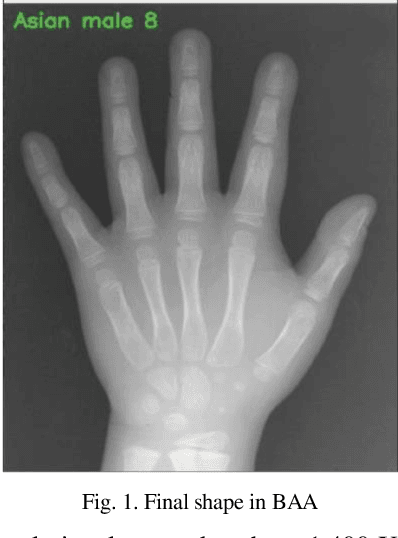

Abstract:Patient skeletal age estimation using a skeletal bone age assessment method is a time consuming and very boring process. Today, in order to overcome these deficiencies, computerized techniques are used to replace hand-held techniques in the medical industry, to the extent that this results in the better evaluation. The purpose of this research is to minimize the problems of the division of existing systems with deep learning algorithms and the high accuracy of diagnosis. The evaluation of skeletal bone age is the most clinical application for the study of endocrinology, genetic disorders and growth in young people. This assessment is usually performed using the radiologic analysis of the left wrist using the GP(Greulich-Pyle) technique or the TW(Tanner-Whitehouse) technique. Both techniques have many disadvantages, including a lack of human deductions from observations as well as being time-consuming.